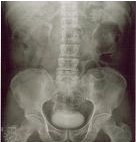

경정맥 신우조영술(IVP)

암이 요관, 방광, 요도 등의 장기에 침범했는지 확인하기 위한 검사입니다.

경정맥 신우조영술 사진 이미지

[경정맥 신우조영술 사진]